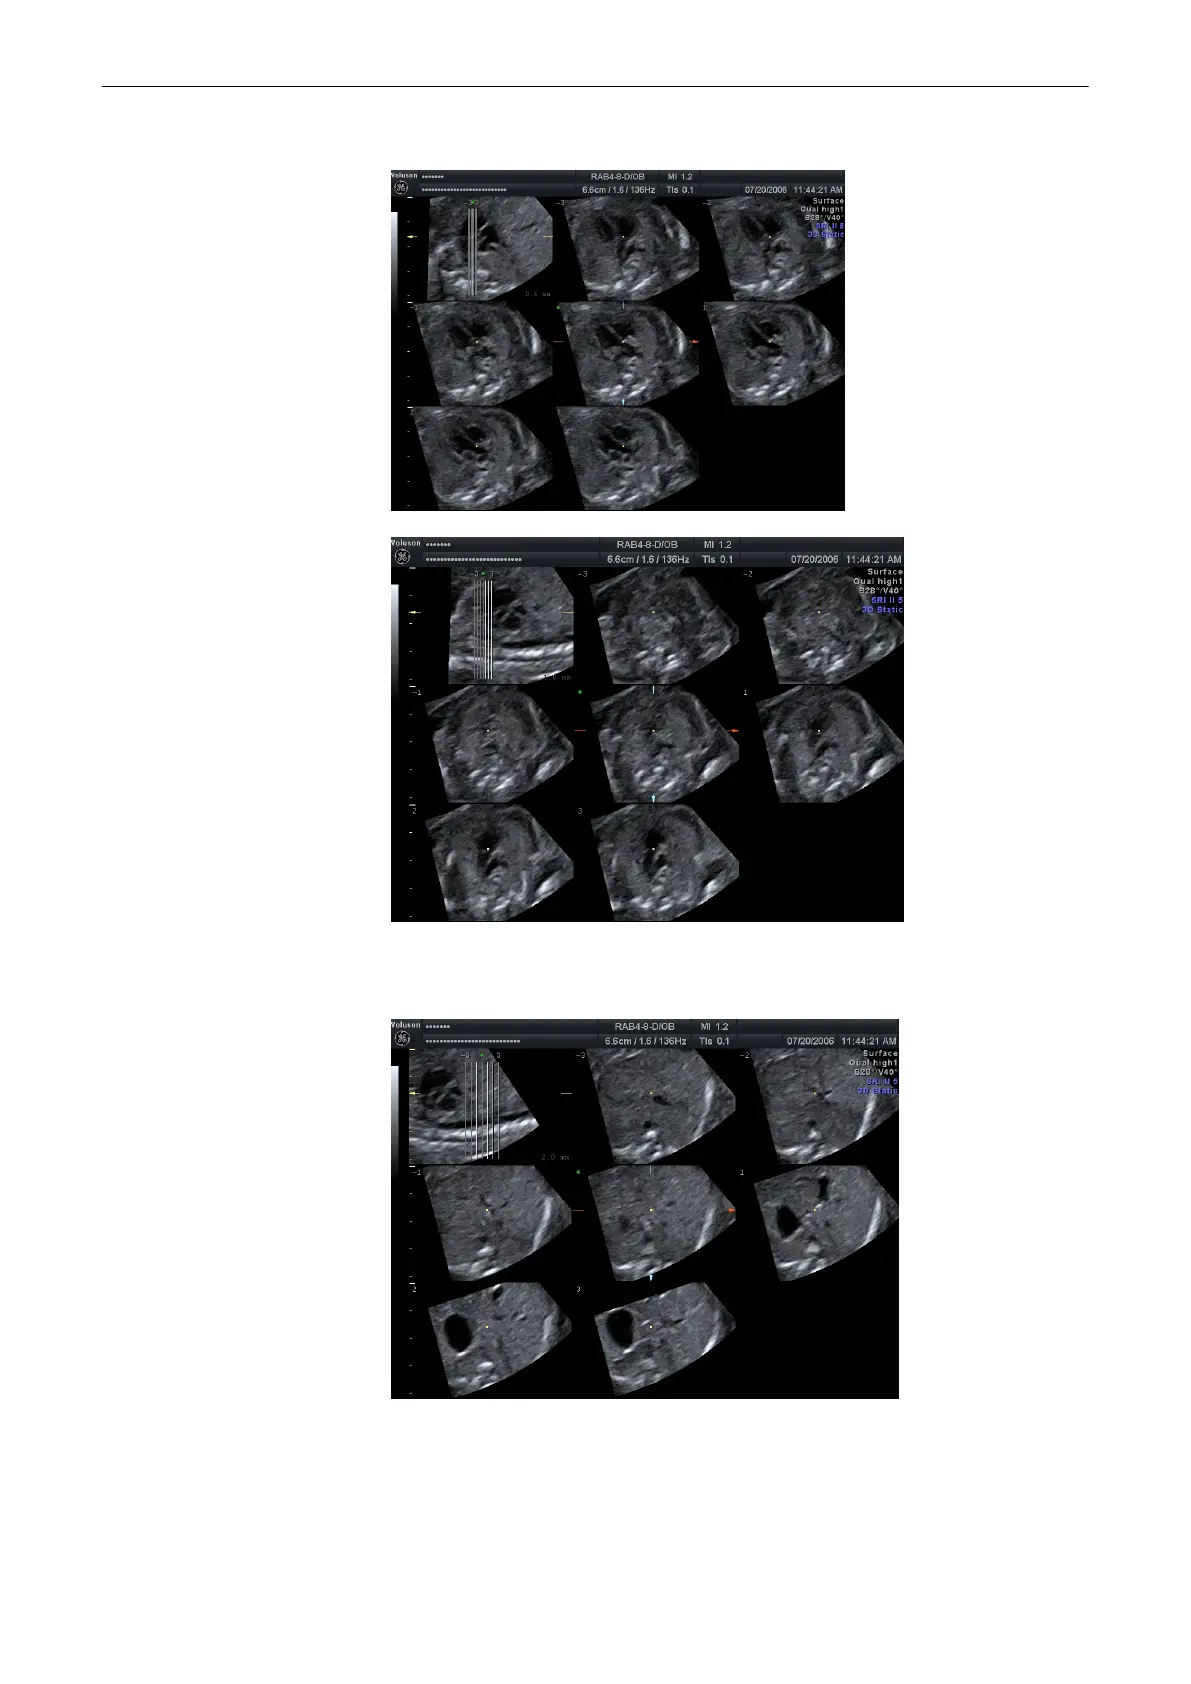

Press [Cardiac 1] to view the left outflow tract.

Or press [Cardiac 2] to view the right outflow tract,

or press [Cardiac 3] to view the fetal stomach.

or press [Cardiac 6] to view the fetal aortic arch